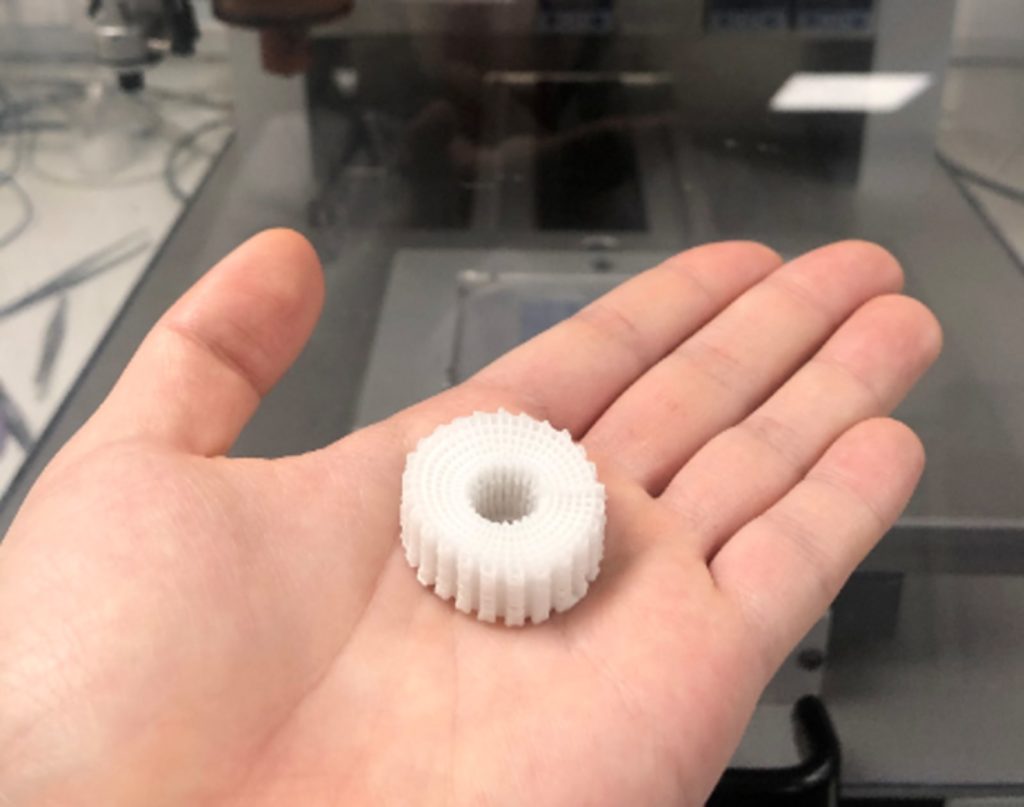

These bone bricks are designed to click together like Lego bricks, creating a personalized fit for blast victims at a time of critical need at Syrian refugee camps.

This is where the newly conceived 3D-printed bone bricks come in. The treatment uses medical scaffolds made of polymer and ceramic materials, which can be clicked together to create a temporary structure that perfectly fills the bone gap caused by the blast injury. These bone bricks would have all the support of a normal bone in compression, while inducing the formation of new bone tissue around the structure. As the bone regenerates, the bricks dissolve. Each of these degradable bricks has pores containing antibiotic ceramic paste, which combats infection in a remarkably practical way during the healing period.

This limb-salvaging solution uses low-cost 3D-printing technology and can be executed in a relatively straightforward manner. All a clinician has to do is piece together a collection of ready-made bricks to create a custom-fit structure for a particular defect. The treatment is expected to cost less than USD$245 (GBP£200) for a typical 100mm fracture injury, as opposed to other methods which can cost anywhere from $330 to $1,230 (£270 to £1,000).